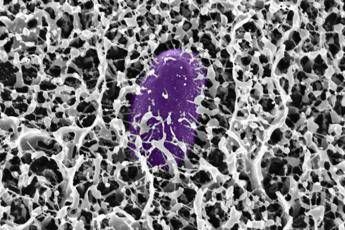

I ricercatori hanno scoperto che quando la Salmonella enterica viene esposta alla mucina MUC2, il batterio interrompe la produzione delle proteine codificate sull'”isola di patogenicità 1” (Salmonella pathogenicity island 1, SPI-1), essenziali per il sistema di secrezione di tipo 3 (T3SS) che permette al batterio di infettare le cellule ospite. Ulteriori analisi hanno rivelato che la MUC2 raggiunge questo risultato disattivando una proteina batterica di regolazione cruciale, nota come HilD. Bloccando questa proteina, la mucina impedisce l'attivazione dei geni T3SS. Utilizzando simulazioni computazionali, è stato dimostrato che alcuni monosaccaridi, come GlcNAc e GalNAc, possono legarsi al sito attivo della proteina HilD. Tuttavia, lo spegnimento dei geni avviene solo quando questi glicani sono ancorati alla spina dorsale peptidica della mucina. Lo studio ha inoltre rivelato che una mucina simile, la MUC5AC, presente nello stomaco, condivide questa capacità. I ricercatori dell'MIT, guidati da Katharina Ribbeck, Andrew and Erna Viterbi Professor of Biological Engineering e autrice senior dello studio, intendono ora esplorare l'uso di versioni sintetiche di queste molecole per potenziare le difese naturali del tratto gastrointestinale.

Come ha spiegato la ricercatrice Kelsey Wheeler, co-autrice principale dello studio: “I mimic della mucina brillerebbero in particolare come preventivi, perché è così che il corpo ha evoluto il muco, come parte di questo sistema immunitario innato per prevenire l'infezione”. La strategia si basa sull'idea di rafforzare le barriere mucose nelle aree del tratto gastrointestinale che la Salmonella tende a infettare. La ricerca è stata sostenuta da diversi enti, tra cui l'U.S. Army Research Office, l'U.S. National Science Foundation e il National Institutes of Health. Immagine di cover per gentile concessione dei ricercatori del MIT —tecnologiawebinfo@adnkronos.com (Web Info)